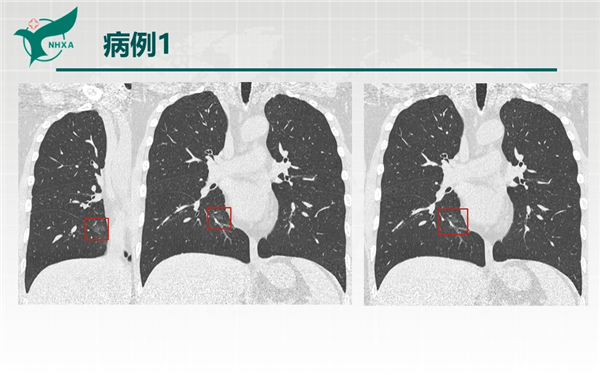

【病例分享】新型冠狀病毒肺炎3例(西安市第九醫(yī)院)

幻燈片2.jpg